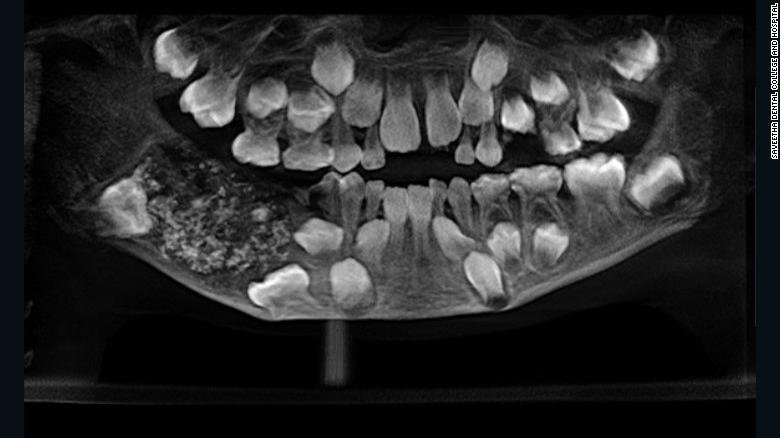

“Kur doktorët i bënë një grafi ata zbuluan një qese të mbushur me dhëmbë anormalë” tha për CNN doktoreshë Prathiba Ramani, kreu i Patologjisë Orale dhe Maksilofaciale në Kolegjin dhe Spitalin Stomatologjik Saveetha.

“Gjithsej 526 dhëmbë të madhësive 0.1 milimetër në 15 milimetër. Edhe dhëmbi më i vogël ka rrënjë kurorë dhe zmalt” tha ajo